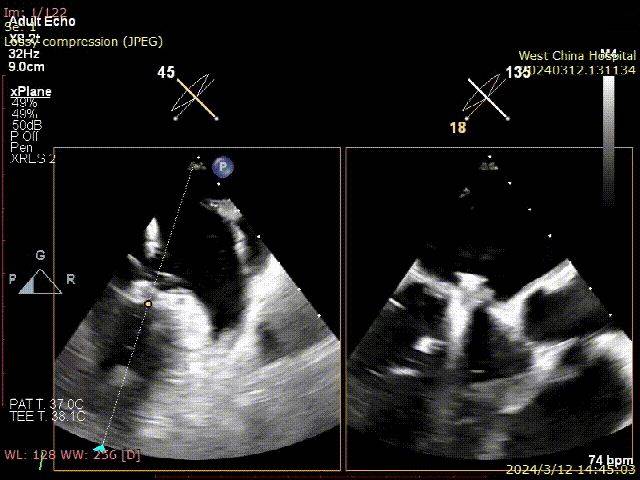

术前TEE:

二尖瓣联合切面

P1&C1 X-plane平面

A3/P3 X-plane平面